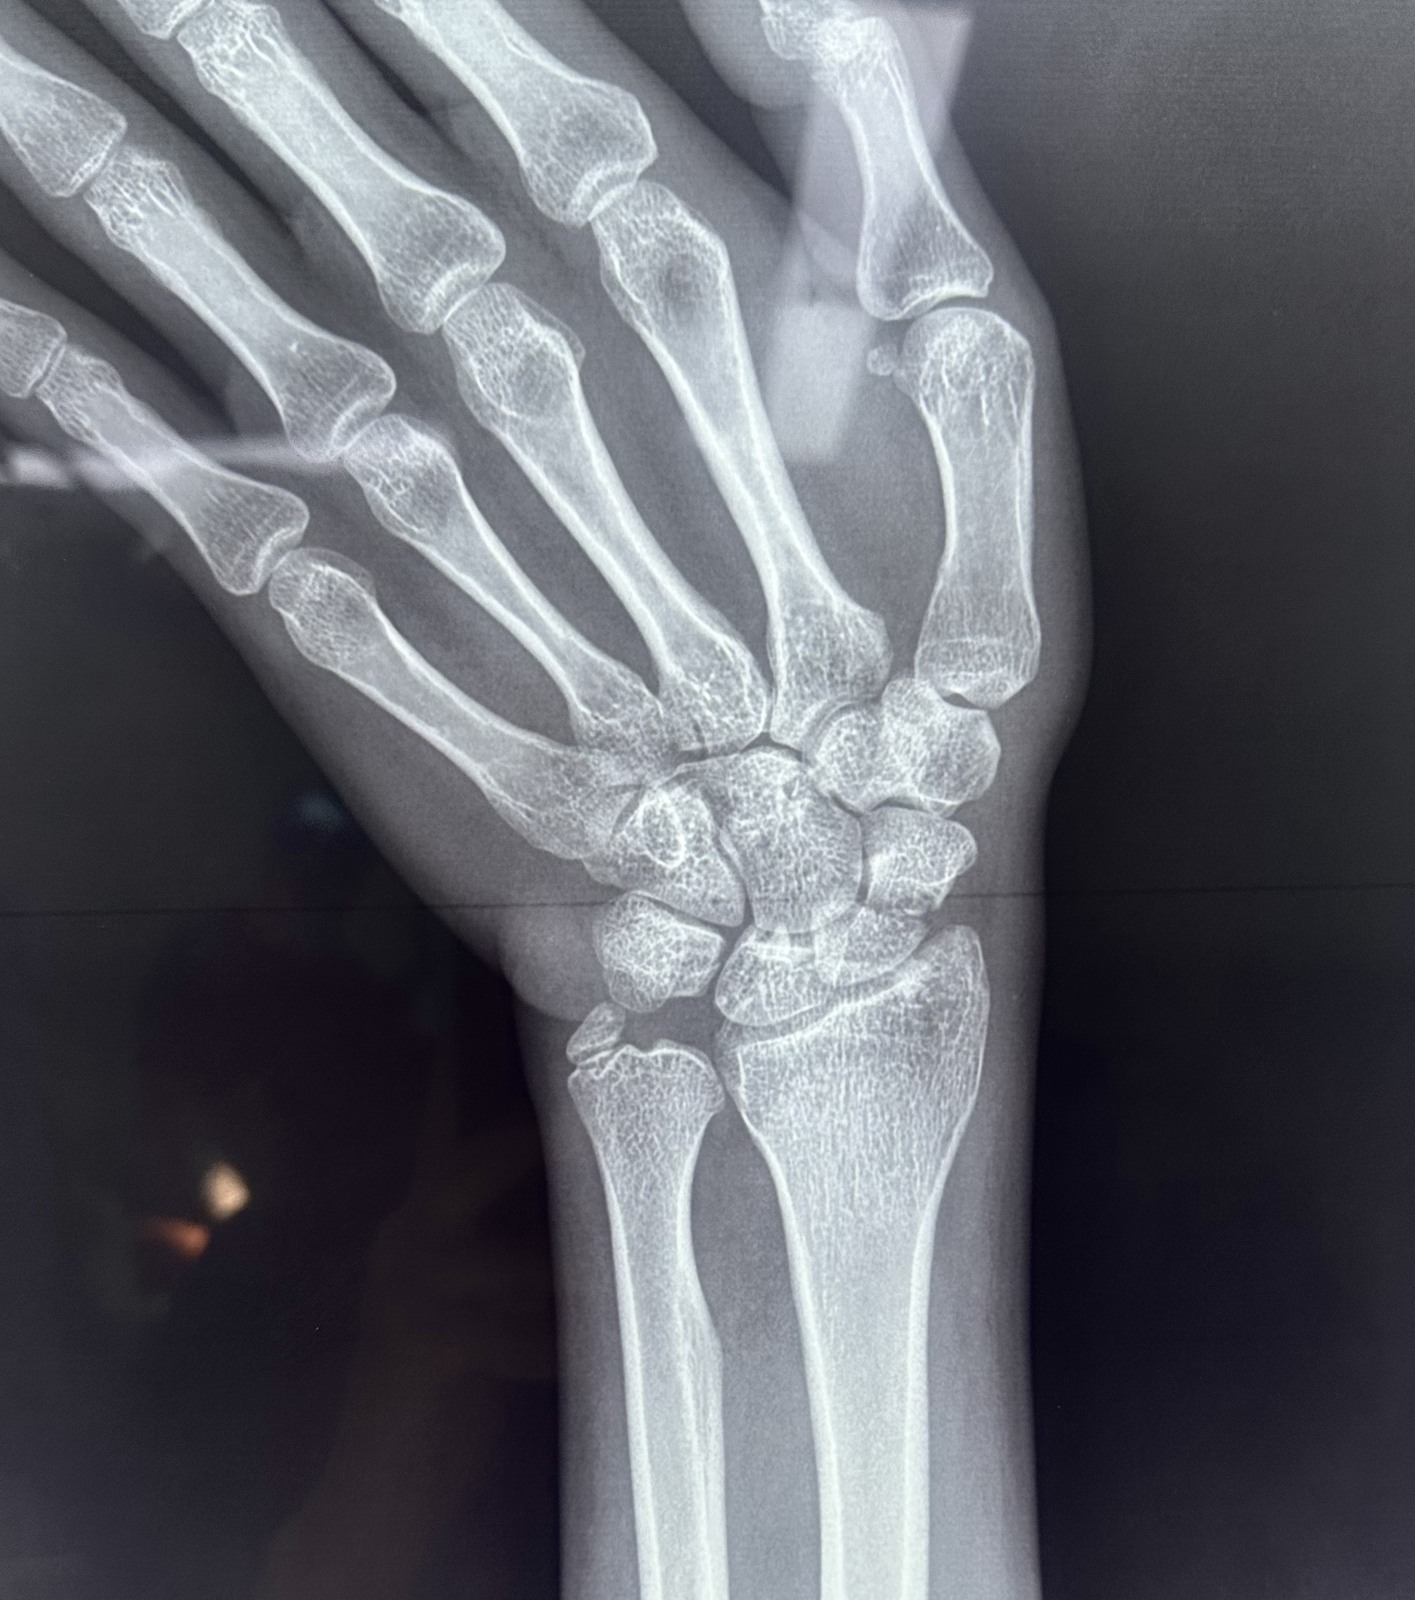

xx 男 36岁 腕舟骨骨折 掌侧切开复位内固定术 。

术前X片显示舟骨腰部骨折

术前X片显示舟骨腰部骨折,AO分型B2型。

掌侧入路

Herbert钉固定